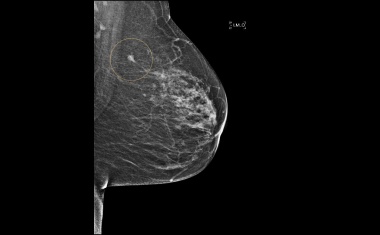

3D-Modell eröffnet Ansatzpunkte für Therapien von Hirnmetastasen nach Brustkrebs

Forscher des Instituts für Klinische Neurobiologie am Universitätsklinikum Würzburg haben ein 3D-Modell entwickelt, das zeigt, wie sich das neuronale Netzwerk durch Hirnmetastasen nach Brustkrebs verändert.